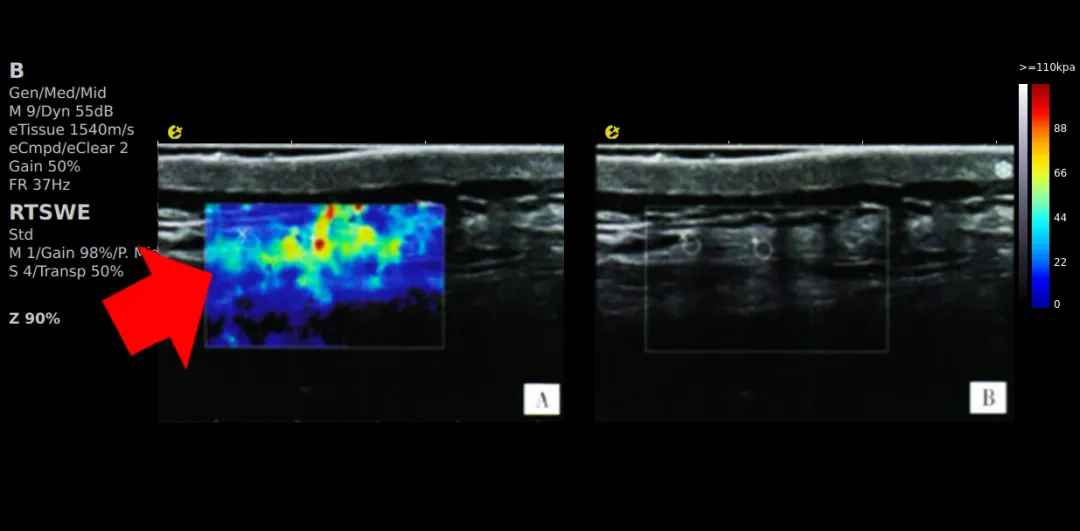

评估治疗效果:

可提供 MTrPs及其正常周围组织的客观指标,为 MPS的疗效评价提供客观依据。如果治疗有效,MTrPs处的硬度会降低,弹性会增加,RTSWE?技术可以通过治疗前后的颜色以及具体数值来对硬度进行对比。王墉琦[3]等利用针刺对腰臀肌筋膜疼痛综合征的治疗研究,证实了超声引导下针刺MTrPs的疗效,也表明弹性模量、杨氏模量及MTrPs与正常组织的应变比(SR)是超声检查的有效客观评价指标。RTSWE?引导的治疗能够有效减轻患者的疼痛,并改善肌肉的弹性。

640 (4).jpg

针刺治疗前后MTrPs点的E成像评估

(A、B坐位,C、D俯卧位)